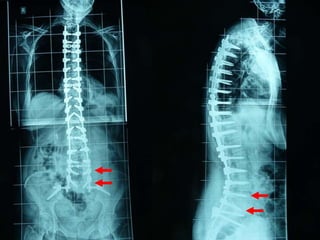

3ος Τύπος Δευτεροπαθής σκολίωση επί

εδάφους μεταβολικών παθήσεων της Σπονδυλικής Στήλης (Οστεοπόρωση) Aebi M. , 2005